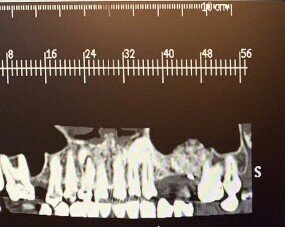

In questo case report è stata selezionata una paziente di sesso femminile, S.P. (54), non fumatrice, con buona igiene orale e con anamnesi negativa all’assunzione di farmaci, ad allergie, disturbi metabolici e patologie sistemiche (Figg. 1-3). È stata proposta una tecnica di rialzo del seno mascellare eseguita mediante strumenti piezoelettrici (Piezosurgery®, Mectron, Genova, Italy) (Figg. 9, 10, 13).

Per la fase post-operatoria sono stati prescritti un analgesico da prendere al bisogno (Paracetamolo 500 mg), cortisone (Bentelan 1 mg, 4 compresse il primo giorno e a scalare i giorni successivi fino ad 1 il quarto giorno) e clorexidina 0.2% e sono state fornite istruzioni complete all’igiene orale. Dopo 7 giorni dall’intervento è stato prescritto nuovamente aerosol (beclometasone dipropionato Clenil 0,8 mg/2 ml) e soluzione ipertonica (Libenar 22g/l per 7 giorni). La sutura è stata rimossa dopo 10 giorni. A distanza di 7 mesi dalla procedura rigenerativa è stato attuato un secondo timing chirurgico per posizionare gli impianti nella sede prestabilita. Eseguita l’anestesia locale sono stati inseriti impianti endossei in posizione 24 (3.2 x 10 mm.) e 26 (4.3 x 10 mm) (JD Evolution Plus - JD Dentalcare, Modena, Italy) (Figg. 17, 18) ed eseguita la radiografia di controllo postoperatoria. La rimozione delle suture è avvenuta dopo 10 giorni.

In seguito all’intervento di rialzo di seno mascellare con contestuale GBR è stata eseguita la radiografia ortopanoramica che mostra il corretto riempimento dell’area atrofica del seno mascellare con granuli cortico-spongiosi di osso di origine bovina. Al controllo dopo tre settimane i tessuti molli dell’area trattata risultano perfettamente guariti. La TC Dentalscan effettuata dopo 6 mesi per il controllo della zona rigenerata evidenzia la perfetta guarigione della zona con aumento dello spessore osseo di 5 mm e dell’altezza ossea di 11 mm.